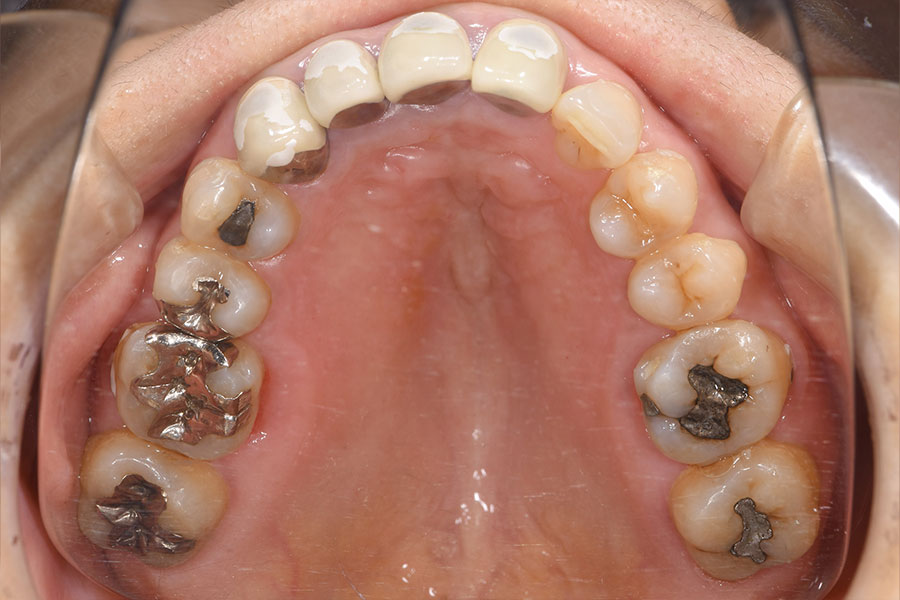

Before -上顎-

| 施術内容 | 金属アレルギー予防を目的に、金属フリーの自費補綴へ変更。適合性・清掃性・審美性の向上が得られています。 |

|---|---|

| 治療期間 | 約4ヶ月 |

| 費用 | オールセラミッククラウン 264,000円 オールセラミックインレー ハイブリットインレー 275,000円 |

| リスク・副作用 | 治療にともない、歯の破折や歯質の削合、場合によっては抜歯が必要となることがあります。また、金属や補綴物を除去する際に、完全に除去できない場合もあります。 |